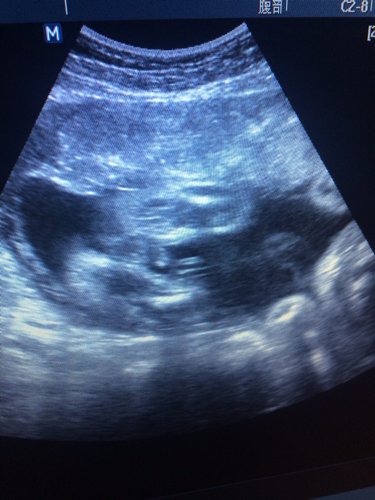

请有经验的医生帮忙看看这张b超图到底是男宝还是女宝? 点击展开 匿名用户 2015-04-05 19:50 为您推荐: 其他回答 你好,根据超声检查的结果,现在判断不出胎儿的性别,如果现在检查,结果比较正常,可以判断胎儿发育和状态比较正常的,平时需要注意休息,加强营养。 cn#BBVGkaafBB 2015-04-05 19:51 相关问题 谁懂b超帮我看下三个月图,是男宝还是女宝,谢谢 我现在先兆流产,我该怎么办,希望医生帮帮我,我把我的B超验血图拍下来了,帮忙看看 那位医生能帮我看一下一张B超图有问题吗?这家医院的医生还是不能排除宫外孕?